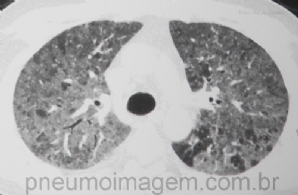

CASO CLÍNICO #12

Paciente do sexo masculino, 45 anos, apresenta-se com dispneia progressiva há um mês e com piora nos últimos dias, febre e emagrecimento. Deu entrada à Emergência com dessaturação, estertoração em ambos os pulmões até os terços médios e DHL no sangue de 1440UI...